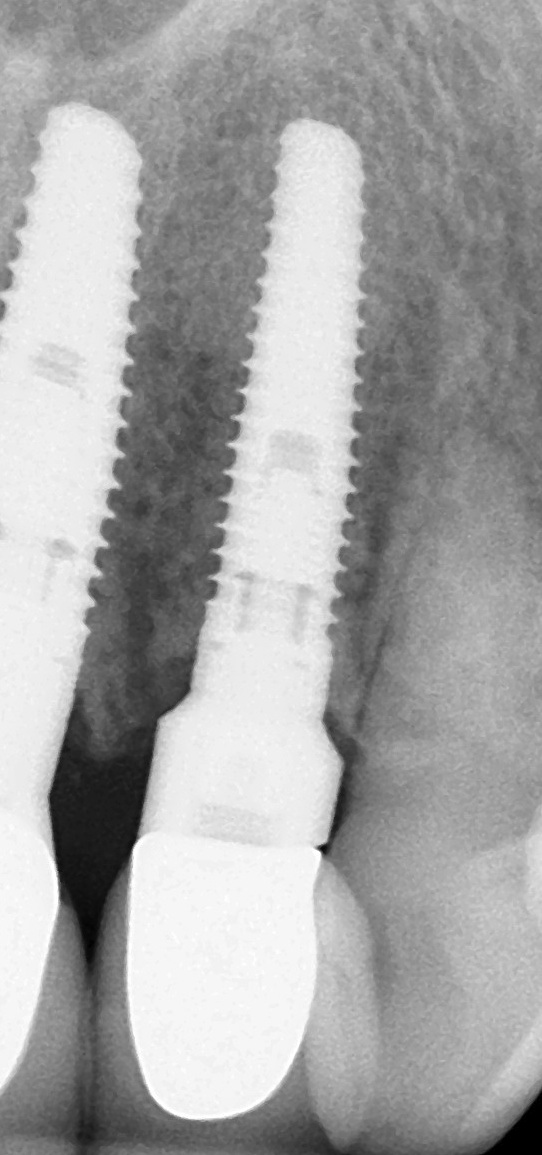

With all of the success seen in the dental community relative to implant placement, dentists are now seeing a more pronounced trend in dental implant care: an increase in the bacteriologic and/or traumatogenic occlusion-mediated loss of tissue integrity, accompanied many times by alveolar bone loss. The most common terminology applied to this condition is peri-implantitis (Figure 1). As replete as the dental literature is with success story after success story, there is virtually no detailed and specific prospective clinical trial data on the diagnosis and management of the peri-implant diseases, which result in soft tissue inflammation and the potential for alveolar bone destruction that may lead to the loss of the implant.

Fig 1. This implant was placed in March 2006. Peri-implantitis was clinically evident in April 2008, with bleeding on probing, suppuration, and increasing probing depth.

Figure 1